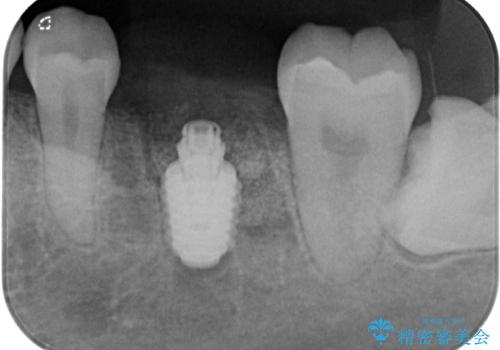

- 食事中に奥歯が痛むとのことで来院された患者様です。

レントゲンやCTより、深くまで破折していることが分かり、抜歯が必要な状態でした。

歯槽骨の状態は良好であったため、抜歯即時埋入インプラントによる補綴治療を行うこととしました。